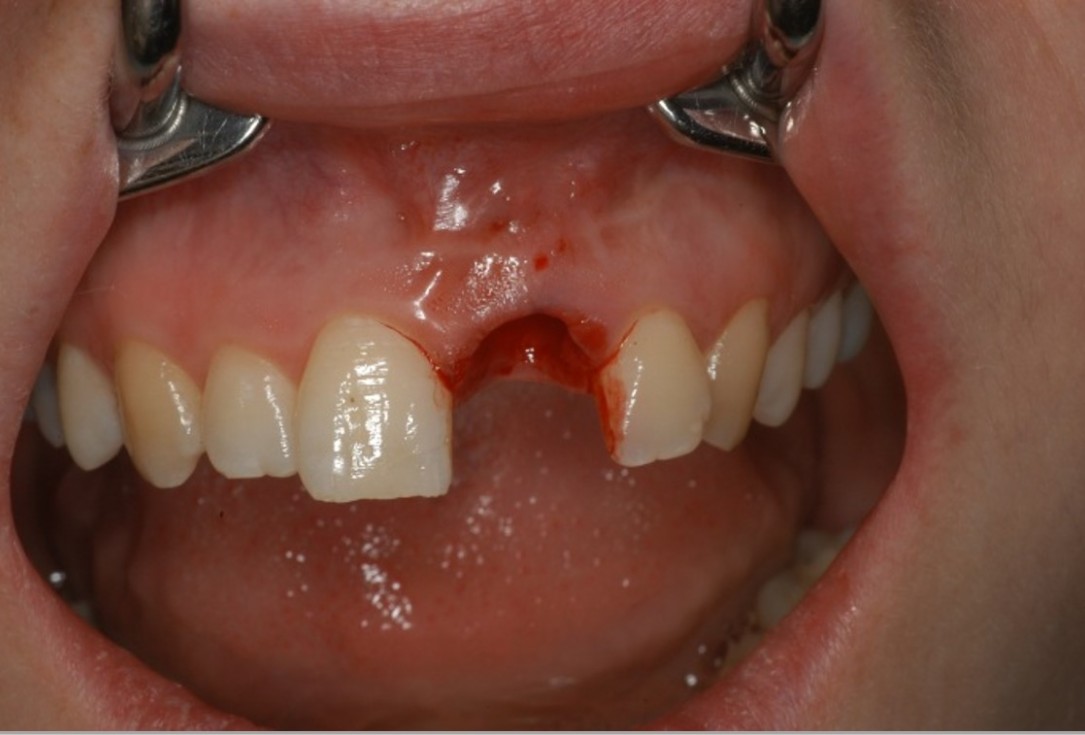

01/12 - Extraction of tooth 21 after endodontic treatmentTreatment of dehiscence defect with cerabone® & Jason® membrane - Dr. M. Steigmann

02/12 - Extraction of tooth 21 after endodontic treatmentTreatment of dehiscence defect with cerabone® & Jason® membrane - Dr. M. Steigmann